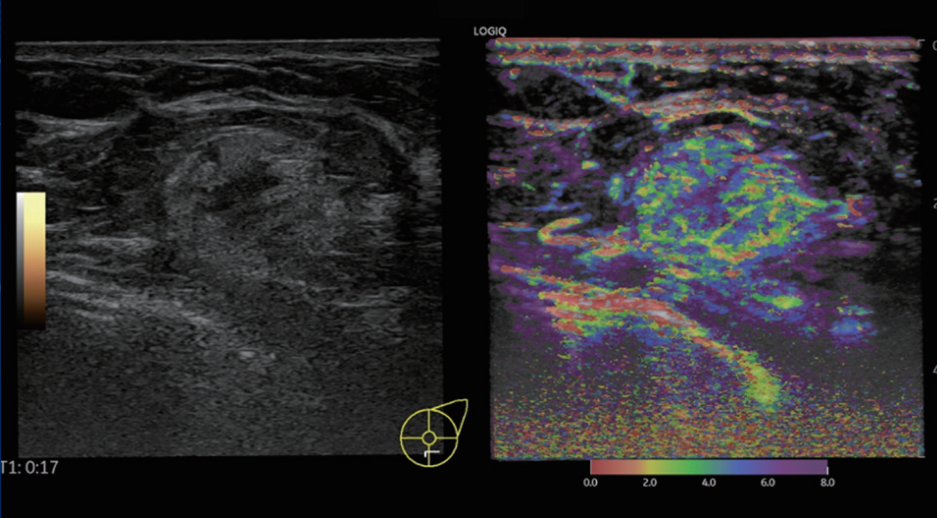

在原始数据处理技术的基础上,将造影剂到达时间设定为不同颜色,叠加显示在造影图像上,即为造影参量成像。即使在一幅静态的造影图像上,也能分辨出造影剂灌注的先后顺序。这使病灶增强模式显示得更加直观,降低了造影图像解读难度,利于总结病灶造影剂灌注特点。